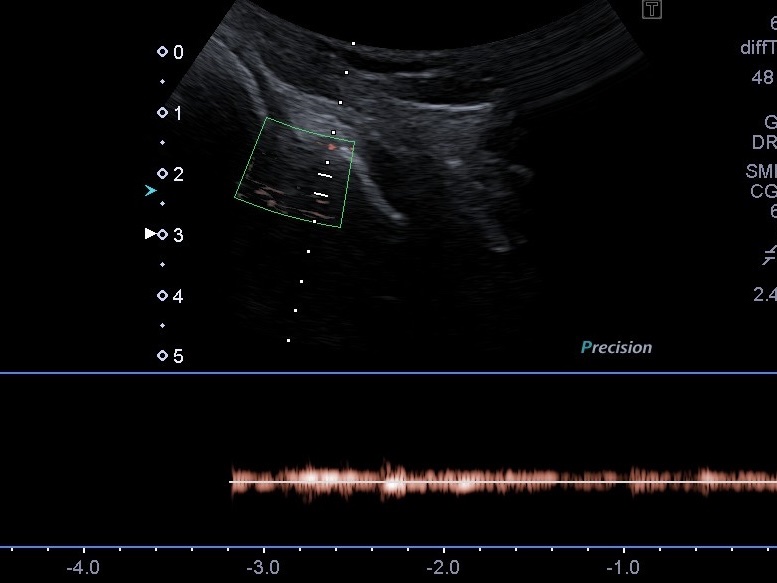

- Эластография сдвиговой волны: Позволяет увидеть процесс фиброзирования разрыва и изменение жесткости мениска при заживлении.

- Режим SMI (визуализация микроциркуляторного русла): С его помощью мы определяем кровоснабжение в «красной зоне» мениска, а также фиксируем появление неоангиогенеза в «белой зоне» после разрыва.

На обычном УЗИ отличить эти зоны невозможно. Однако включение режима SMI позволяет разграничить их по наличию доплеровского сигнала от микроциркуляторного русла. Иногда сосуды из красной зоны начинают мигрировать внутрь разрыва — это признак восстановления, который мы можем зафиксировать и отследить в процессе лечения.